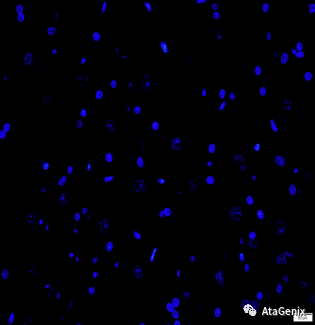

技术资料图片4

a-Rat cerebellum-DAPI staining

技术资料图片5

b-mouse anti detyrosinated alpha tubulin staining

技术资料图片6

c-Merged

杂交瘤技术生产的TUBA3鼠单抗在大鼠小脑组织石蜡切片的IF验证结果。